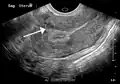

-

A very large (9 cm) fibroid of the uterus which is causing pelvic congestion syndrome as seen on ultrasound -

A small uterine fibroid seen within the wall of the myometrium on a cross-sectional ultrasound view -